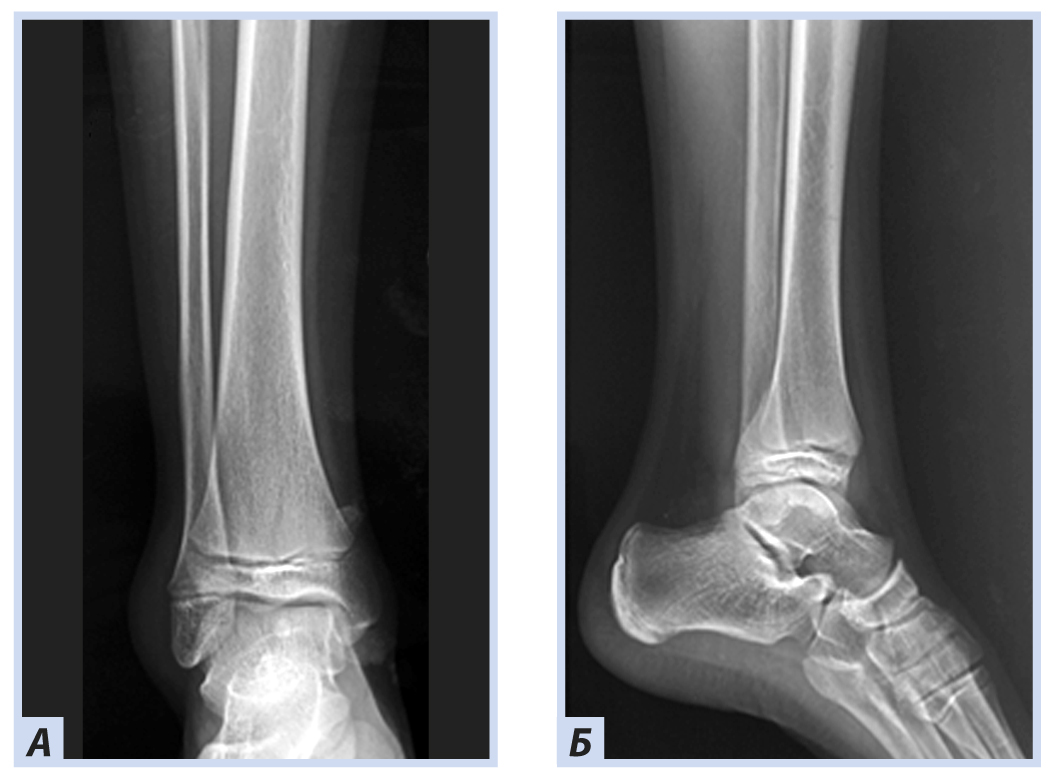

Клиническое наблюдение 3

Мальчик, 16 лет, диагноз «Закрытый перелом обеих лодыжек правого голеностопного сустава с подвывихом стопы кнаружи. Супинационно-эверсионный механизм травмы». Травма получена в результате падения на льду. По данным ультразвуковой диагностики был диагностирован частичный разрыв передней порции дистального межберцового синдесмоза. Выполнен остеосинтез внутренней лодыжки спицами, дистальный межберцовый синдесмоз фиксирован синдесмозной системой (Arthrex Tightrope Ankle), перелом латеральной лодыжки фиксирован 1/3 трубчатой пластиной. Внешняя иммобилизация осуществлена гипсовой лонгетой. Контрольная рентгенография и исследование микроциркуляции в области перелома методом лазерной допплеровской флоуметрии выполнены через 8 нед. после операции. На рентгенограммах имеются признаки зажившего перелома, по данным флоуметрии наблюдается активация капилляризации тканей и нутритивного кровотока в условиях регенераторного процесса. Спицы удалены через 8 нед., конфигурация сустава восстановлена полностью (рис. 10–13).

Рис. 13. Тот же пациент. Рентгенограммы дистального отдела костей правой голени через 8 нед. Консолидация костных отломков: А — прямая проекция; Б — боковая проекция.